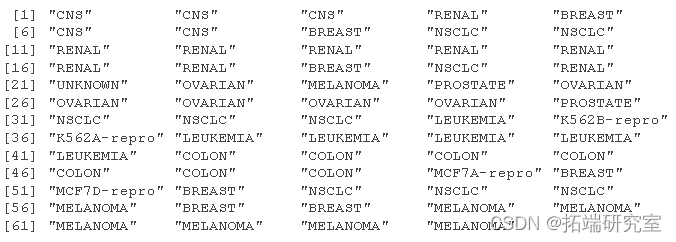

table(ncibs)

ncbs

我们可以看到一个清晰的模式,即所有白血病细胞系都属于聚类 3,其中乳腺癌细胞分布在三个不同的聚类中。